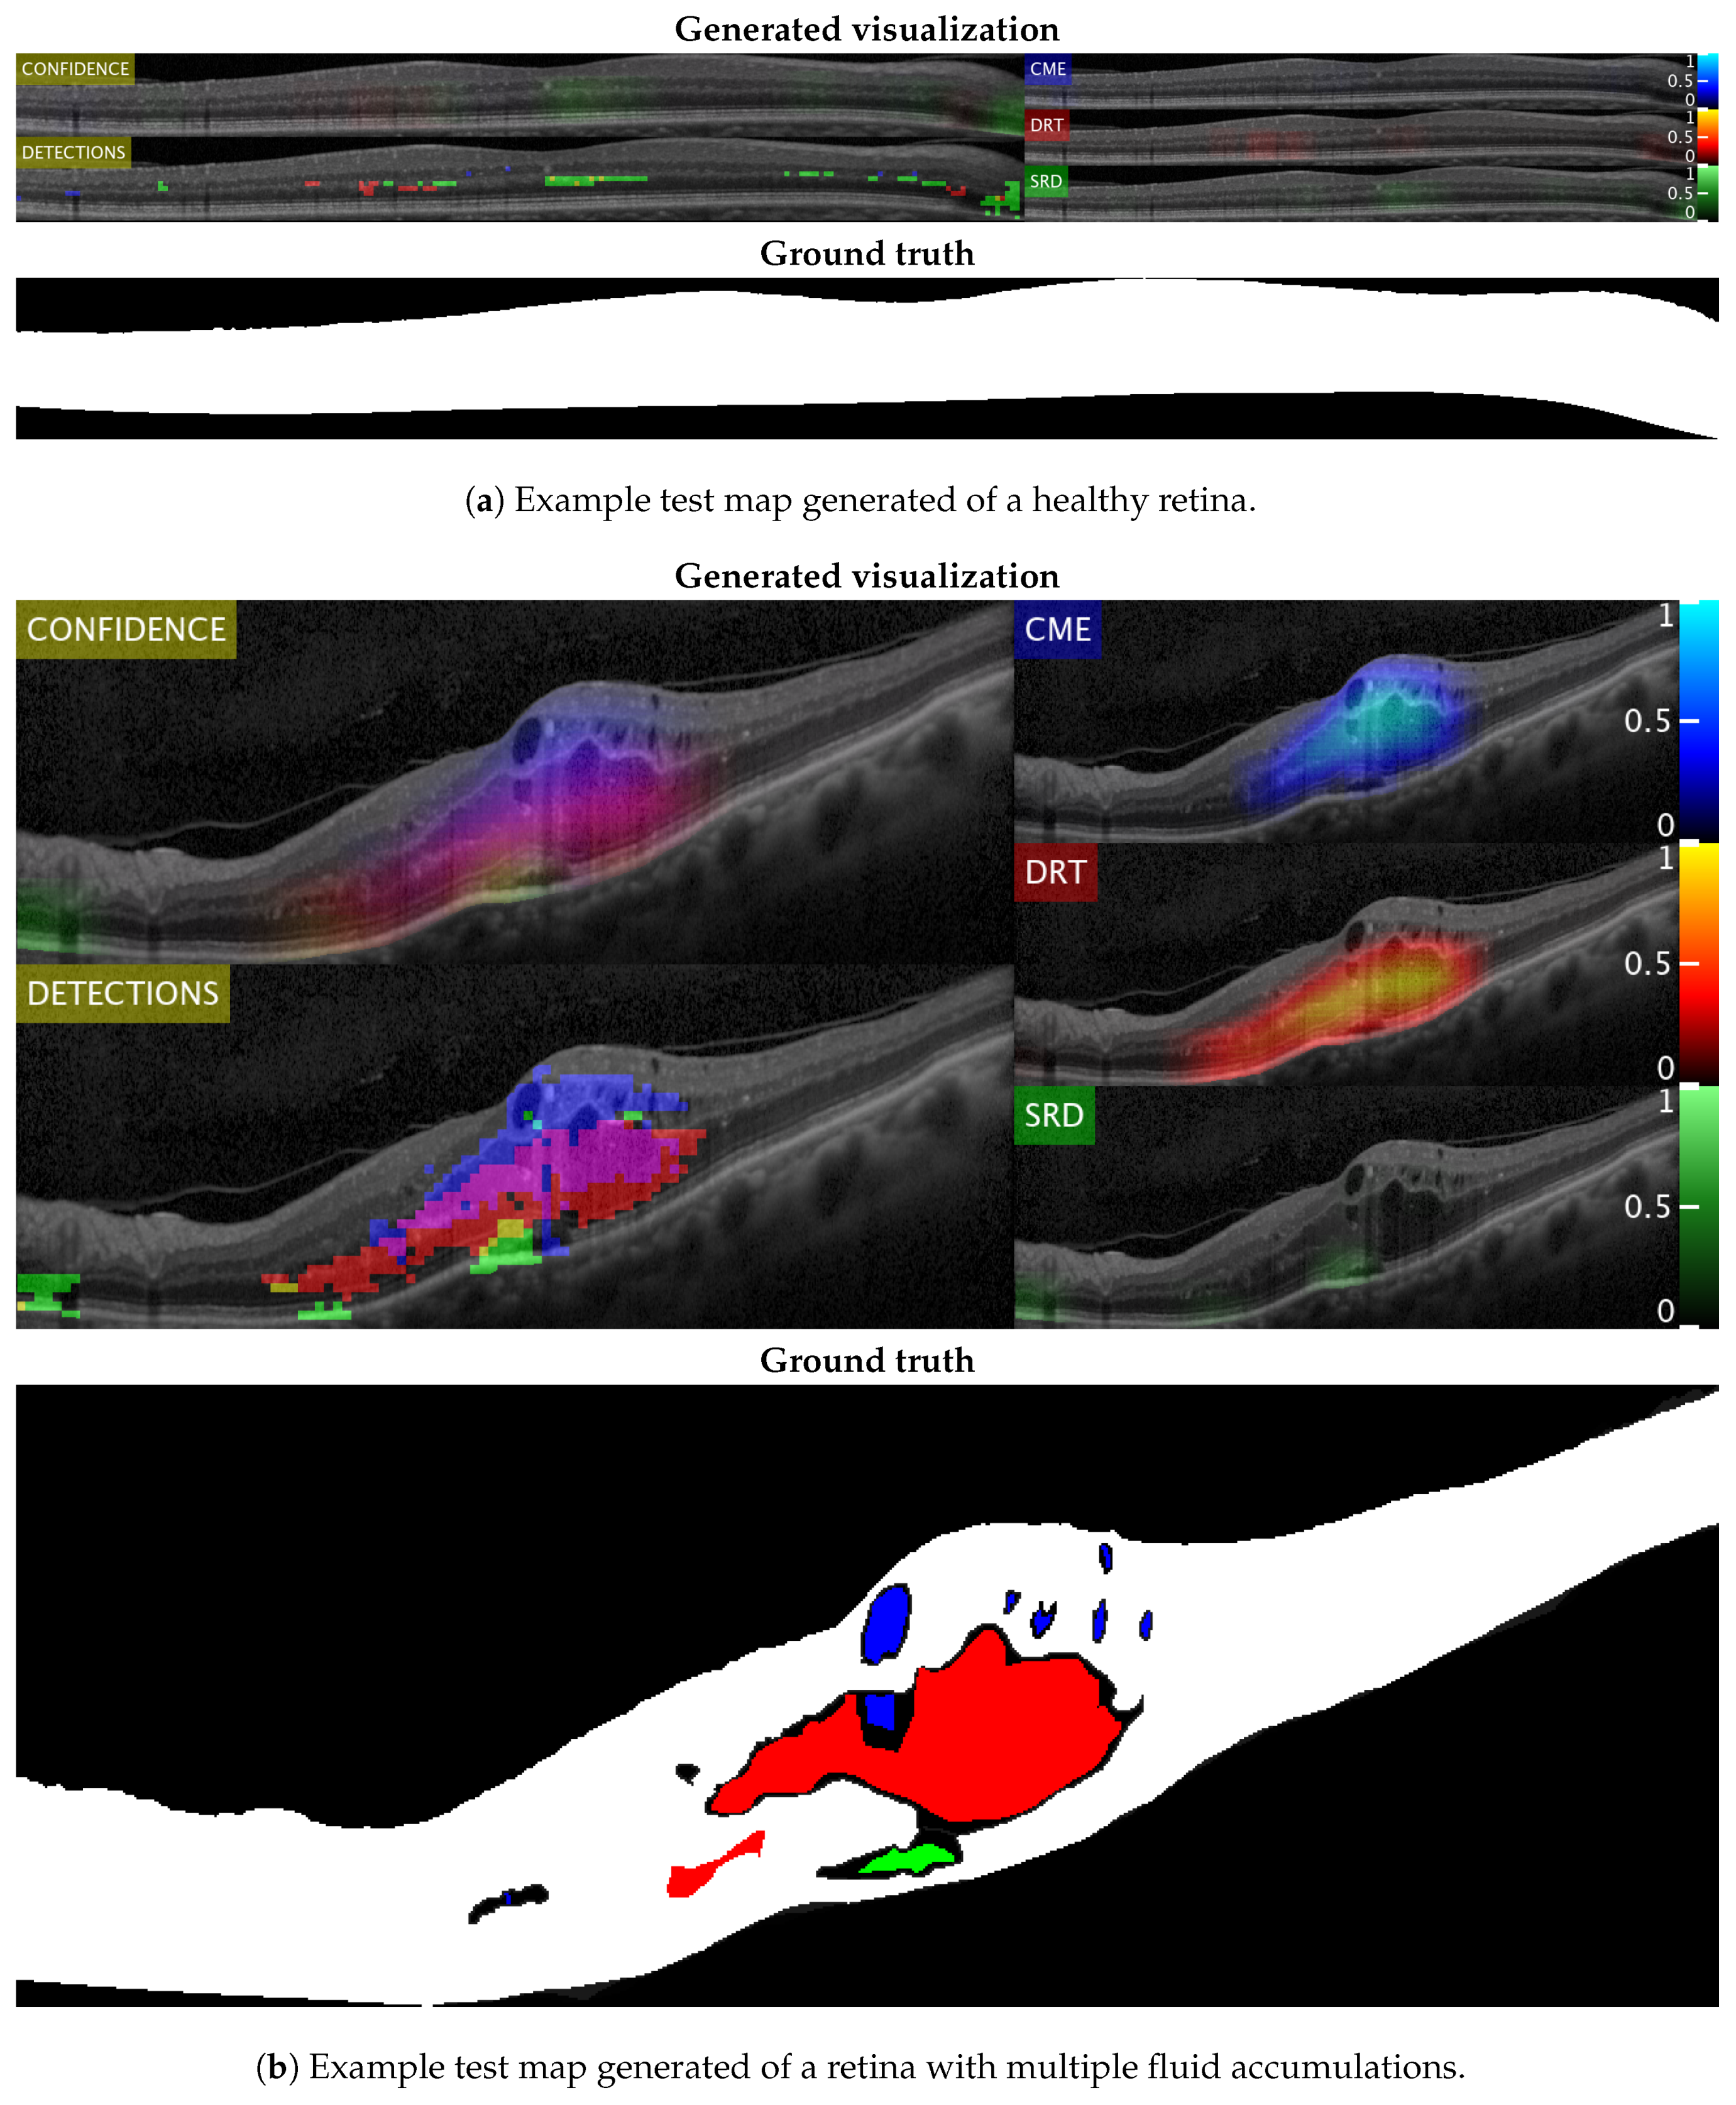

Figure 14 and Figure 15 show representative examples from the test set with a healthy image and another one with different types of pathological fluid generated with the Spectralis and Cirrus devices, respectively. In addition, the labels of the expert are included to compare with the results. As can be seen, in both cases, the system is capable of satisfactorily detecting the pathological fluid accumulations whenever they are present, although we can see spurious detections in the cases of both Figure 14a and Figure 15a. However, these detections can be easily corrected with post-processing strategies as mentioned before, but we decided to include them for a better understanding of the behavior of the system.

Figure 14.

Test visualizations generated using images from the Spectralis device.

Figure 15.

Test visualizations generated using images from the Cirrus device.

In these visualizations, we can observe two major phenomena. The first one consists in the tendency to spurious detections in the images generated by the Spectralis of the SRD-type edema. This may be due to the higher contrast of the images generated by this device, favouring the appearance of common patterns of the SRD-type edema not present in the images that are generated with Cirrus. On the other hand, we can see a clear tendency in the Cirrus images to generate small detections of DRT-type edema. This is due to what was already mentioned in the section where we analyzed the selection of features: the DRT pattern of the images that are generated with the Cirrus device is very similar to the normal tissue in comparison with the "wet" and coarse texture of the DRT fluid accumulations in images that are generated with the Spectralis device.